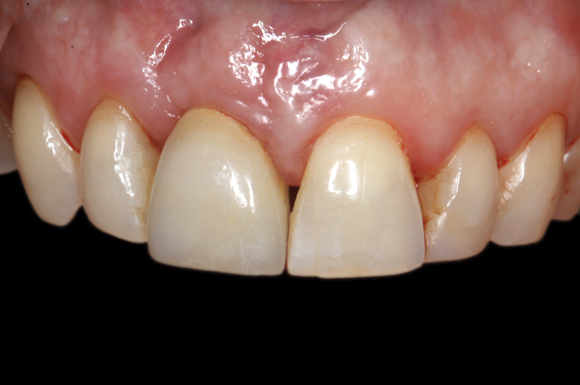

(26.) Facial and occlusal views of the soft-tissue contour achieved after 3 months of provisionalization. The tissue is thick with a harmonious gingival contour and zenith position.

Figure 26

(27.) Facial and occlusal views of the soft-tissue contour achieved after 3 months of provisionalization. The tissue is thick with a harmonious gingival contour and zenith position.

Figure 27